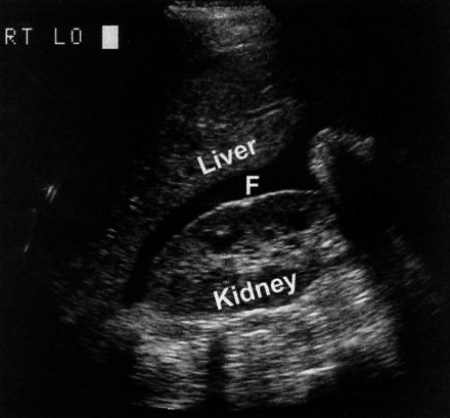

Фото 3. Жидкость в правом верхнем квадранте живота. На продольном ультразвуковом изображении наблюдается свободная жидкость (F) в брюшной полости (кармане Моррисона) – между почкой и печенью